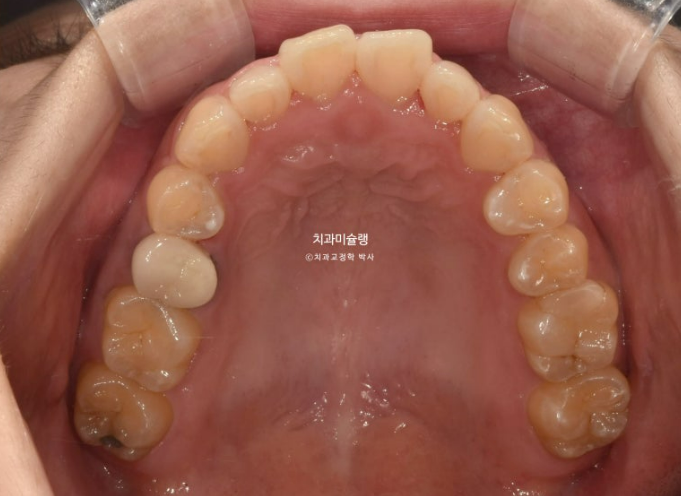

20년 전 교정을 했는데 재발이 되어 재교정을 위해 온 30대 환자분입니다.

24.06

아래 앞니 두 개 잇몸이 유독 내려가 있습니다.

정중선 기준 한쪽만 개방교합이 있는데 한쪽방향으로 혀내밀기 습관때문에 생긴 개방교합일 수 있고 유지장치 변형에 의해 치열이 일그러진 것 일수도 있습니다.

소구치에 윗니와 아랫니가 엇갈려 물리는 가위교합도 보입니다.

큰어금니 교합도 좋은 편 입니다.

파란화살표는 가위교합 원인 치아입니다.